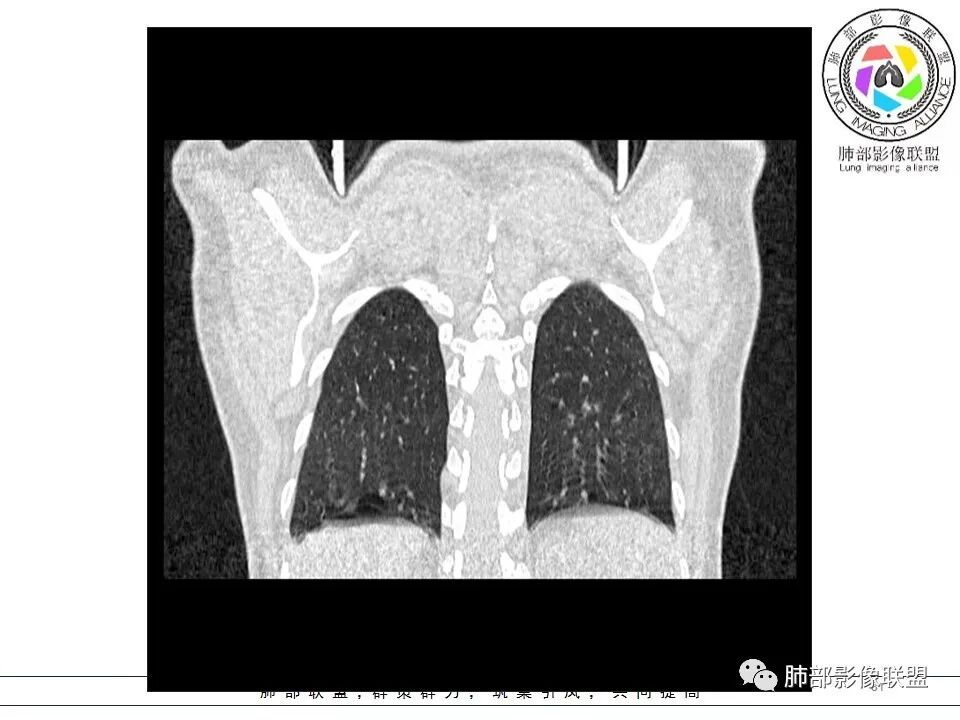

女,38岁,无症状,胸片体检发现两肺可疑病灶。

?其母亲有肺大泡,2017年手术。影像学特点:两肺胸膜下多发的大小不等囊状气腔,壁很薄或无可见的囊壁,小囊的边界比较清楚,大囊的形态比较怪异,以两下肺为著。考虑肺组织细胞增生症,鉴别肺淋巴管肌瘤病。

BHD主要影像表现特征:    1、两肺内肺囊肿:80%以上的BHD患者会出现肺内囊肿,且倾向于基底部近胸膜下分布,特别是纵膈侧肺膜下,囊肿形状不规则、囊肿可大可小,肺内囊肿多毗邻肺下动脉或静脉近端,胸部CT上囊肿分布和特点对诊断有提示意义。    2、继发自发性气胸:BHD患者发生气胸风险是正常人的5倍,BHD患者的气胸发生率约为 1/4,气胸复发率则高达59%。   3、肾肿瘤:(常为双侧性、倾向于嫌色细胞组织学亚型)   4、皮肤表现(为面、颈部纤维性毛囊瘤、毛盘瘤)